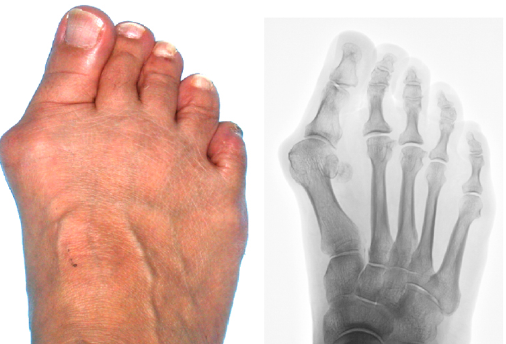

수술

심한 경우, 특히 무지외반증과 같은 상황에서는 수술을 권할 수 있습니다.

- 무지외반증 수술 후 회복 기간은 얼마나 걸릴까요?

- 무지외반증 수술 후 회복 기간은 사람에 따라 다르지만 일반적으로 몇 주에서 몇 개월까지 다를 수 있습니다.